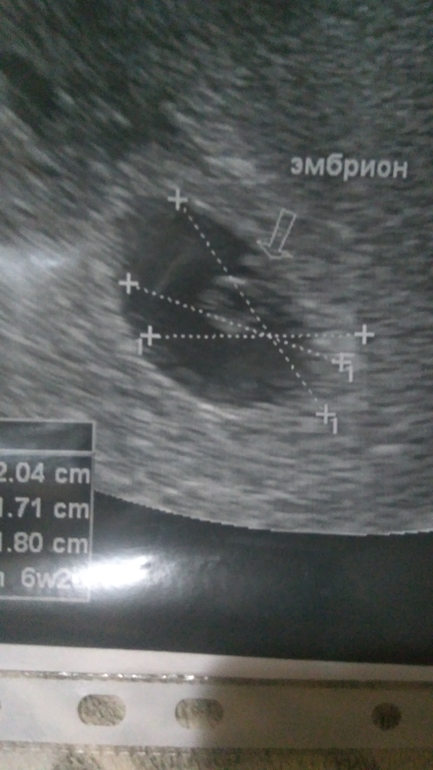

УЗИ, КТГ, доплерНу вот и я сходила на повторное узи, сердечко стучит))) по узи срок 6недель и 2дня))

В прошлый раз мне также не сказали из за того что сердца не слышно было и эмбриона не видно было, вот и сказал прийти через неделю чтобы уточнить все)) овуляция у меня видимо ранняя была срок по М 5нед. и 5дней, а по узи 6недель и 2дня))